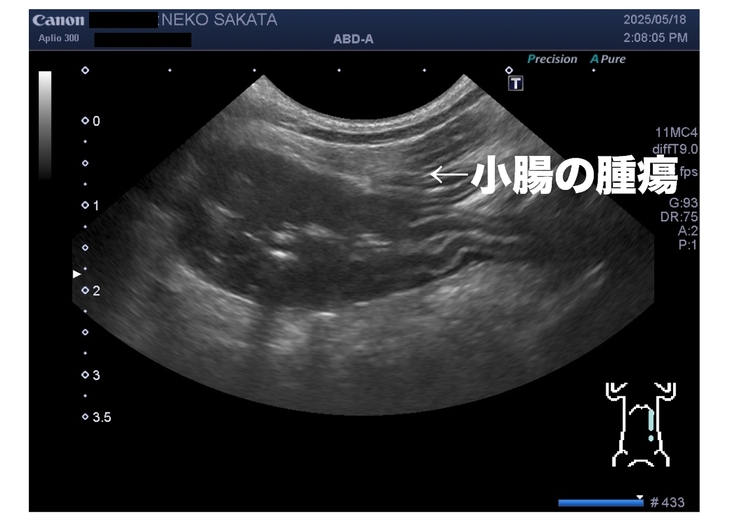

5月18日

かかりつけ病院で再度血液検査とエコーをして貰った。

ここでの血液検査結果も変わらず慢性腎臓病ステージ2の数値だった。

エコーでは嚢胞の大きさは変わらずだったが、

小腸に腫瘍が新たに見つかった。